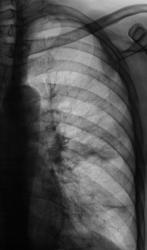

Рентгенограммы и их фрагменты.

Ниже представлены прицельные рентгенограммы пищевода, произведенные в процессе исследования данного пациента, в ортоположении водной взвесью сернокислого бария обычной консистенции.

Ниже рентгенограммы, произведенные на трохоскопе с применением сметанообразной и пастообразной контрастной взвеси.